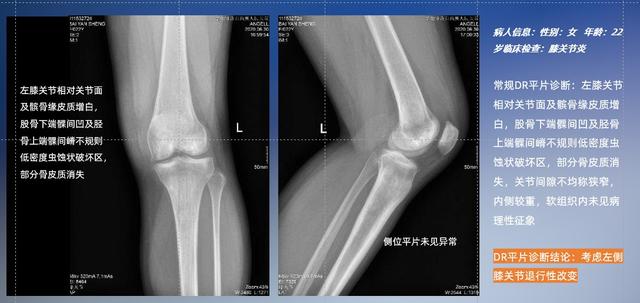

普通平片扫描与WR-3D扫描前后诊断结果对比

在负重位状态下,数字化X线三维扫描与重建,能够更好的呈现受检者关节受力改变的状态。388vip太阳集团科技创新的WR-3D动态三维影像重建系统,通过数字化X线摄影完成三维扫描并重建三维影像信息,包括断层图像重建、MPR多平面重建、MIP重建以及VR体绘制。其扫描时间短,剂量相较于CT设备大幅缩减,同时成本更低,在临床诊断以及医疗方案制定中具有极大的价值意义。而相较于普通平片下的负重位扫描,负重位动态三维影像重建技术能够避免二维状态下的组织结构重叠、密度分辨率不足、组织解剖结构难以分辨等问题。WR-3D支持多角度的三维观察,能全面的呈现被检查部位在多个角度下的三维影像信息,极大的降低了二维负重位检查带来的漏诊率。